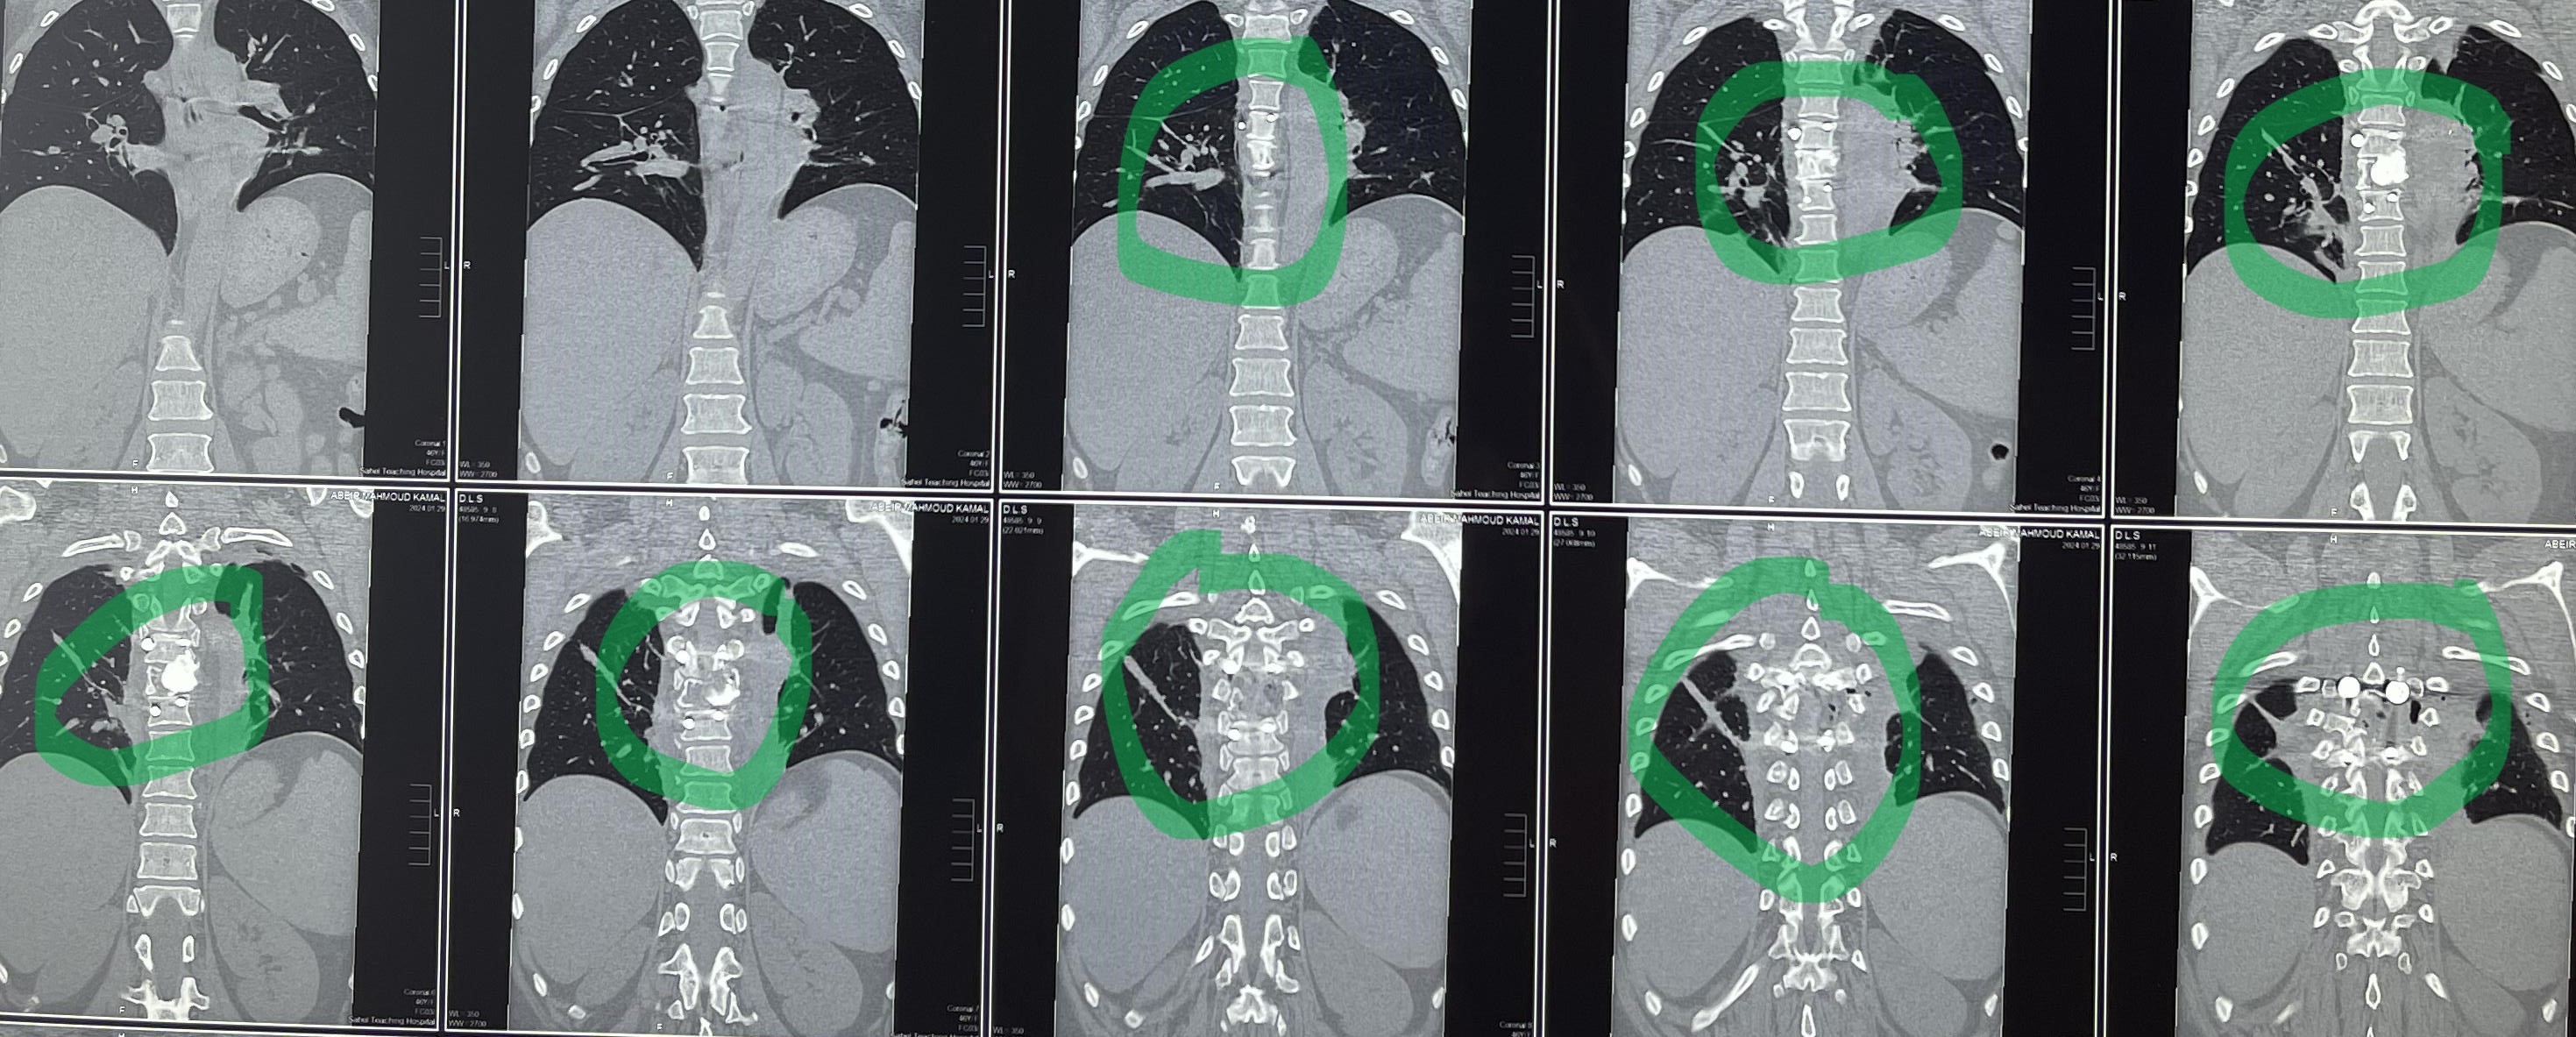

مريضة عمرها 43 عام تعاني من ضعف متزايد بالطرفين السفليين.

43-year-old female patient suffers from increasing weakness in the lower extremities

A 43-year-old woman suffering from progressive weakness in both lower limbs was diagnosed and treated. This condition affects walking ability and mobility, requiring thorough neurological evaluation to determine the underlying cause and develop an appropriate treatment plan.